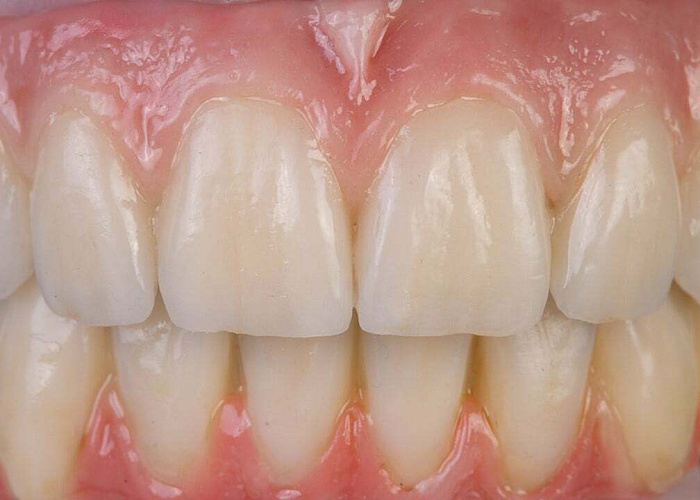

Мягкотканная пластика (базовый уровень): вестибулопластика, ССТ/СДТ, коррекция фенотипа

Москва, Нижний Сусальный переулок, 5с1

Стоимость:

27 900 ₽

Организатор: Implant school

Лектор: Ерохин Алексей Иванович